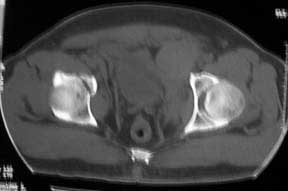

Middle aged male who was injured when a log of wood fell on him ina saw mill. Haemodynamically patient stable. No visceral injuries detected. The following musculoskeletal injuries detected: 1) Closed fracture femur. 2) Pubic symphysis disruption. 3) Right inf pubic rami fracture. 4) Right acetabular fracture. Head of femur located. 5) Right Sacroiliac joint anterior opening.

Your plan sounds fine. The acetabular fracture looks like a high ramus fracture that happens to enter the acetabulum. The CT scan is blurry, and you haven't provided any oblique views of the acetabulum - but my guess is that the 'tab is concentric.